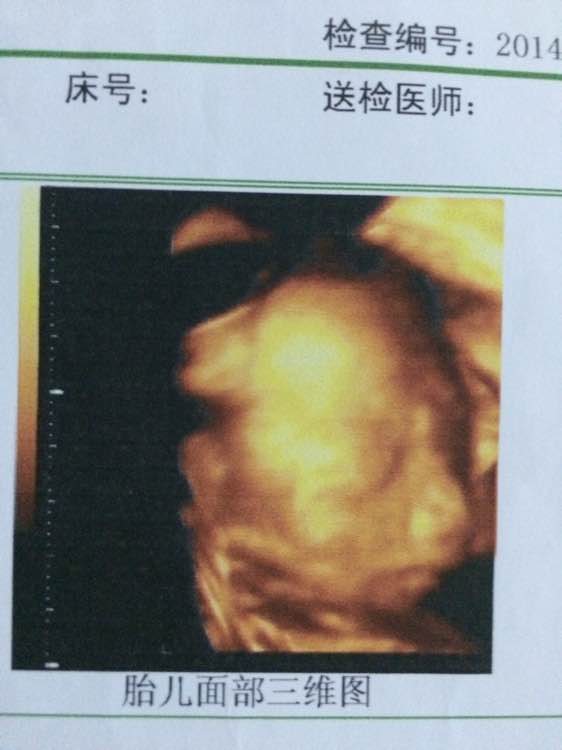

我怎么觉得我娃很黑的样子,而且感觉鼻子好大的样子,五个月的时候的照片,看着像我老公,我老公黑乎乎的,真怕娃出来了也黑乎乎的,楼下放图哈

看着像我老公来着,但是仔细看又觉得下巴嘴巴像我

鼻子是不小

就是啊,五个月就看着好大的样子,以后咋办